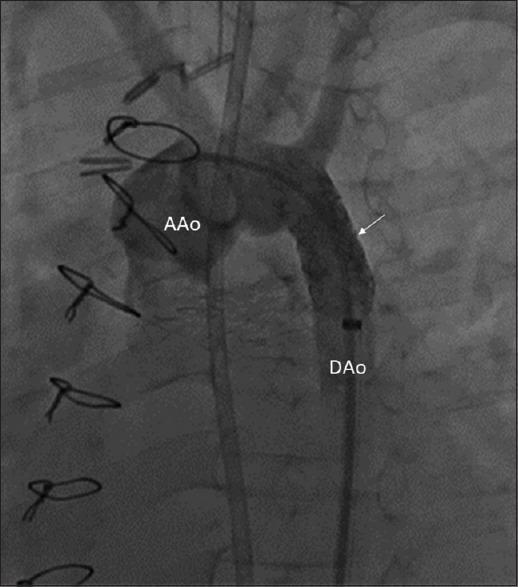

Posterior reversible encephalopathy syndrome (PRES) is a clinical-radiographic syndrome reported in children with hypertension due to renal diseases, immunosuppression after solid organ transplant, cytotoxic agents for chemotherapy, and many others rare instances. We described PRES in a 6-year-old child with hypertension secondary to an incidental postoperative coarctation of the aorta after heart transplantation (HT). Her blood pressure was well controlled with amlodipine during the outpatient visits and home monitoring of blood pressure, but she had hypertension when presented with neurological symptoms. This case's unique feature is that although PRES has been described after pediatric HT, this is the first case report due to a postoperative coarctation of the proximal descending aorta related to scarring from previous multiple sternotomies leading to inadvertent external compression of the aorta with scar tissue. We discussed the risk factors associated with hypertension before PRES and the correlation of brain magnetic resonance imaging findings with clinical outcomes.

后部可逆性脑病综合征(PRES)是一种临床影像学综合征,见于患有因肾脏疾病导致的高血压、实体器官移植后的免疫抑制、化疗用细胞毒性药物等情况的儿童,以及许多其他罕见病例。我们描述了一名6岁儿童,其在心脏移植(HT)后因偶然发生的主动脉缩窄而继发高血压,进而出现PRES。在门诊就诊以及家庭血压监测期间,她的血压通过氨氯地平得到了良好控制,但在出现神经症状时她患有高血压。该病例的独特之处在于,尽管PRES在小儿心脏移植后已有描述,但这是首例因先前多次胸骨切开术形成瘢痕,导致近端降主动脉术后缩窄,瘢痕组织意外对主动脉造成外部压迫而引发的病例报告。我们讨论了PRES发生前与高血压相关的危险因素,以及脑磁共振成像结果与临床结局的相关性。